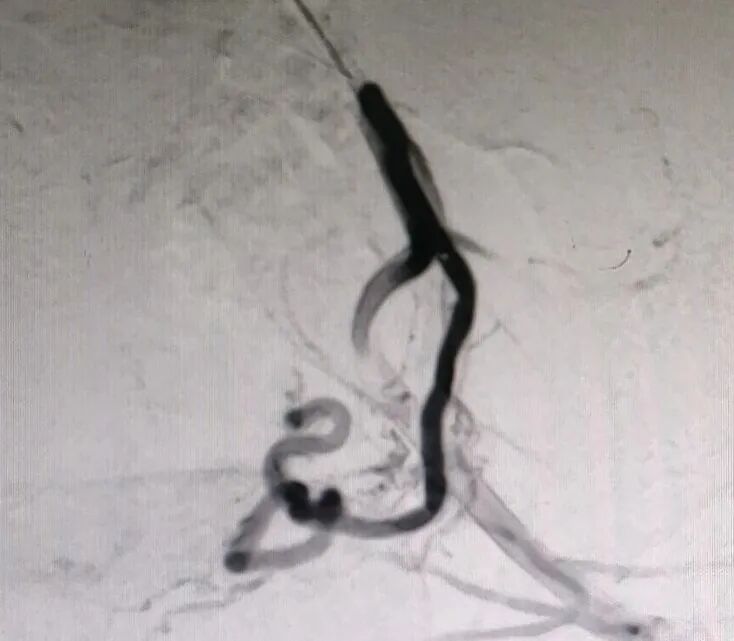

随后,妇产科与介入手术室密切配合为患者在局麻下进行了子宫动脉栓塞术,介入手术过程顺利,术后患者状态良好,生命体征平稳。1天后,妇产科在全麻下为患者进行了宫腔镜下剖宫产瘢痕妊娠清除术,手术顺利,术中出血仅50ml。目前,患者在妇产科医护团队的精心治疗和护理下,已康复出院。

术前栓塞前影像